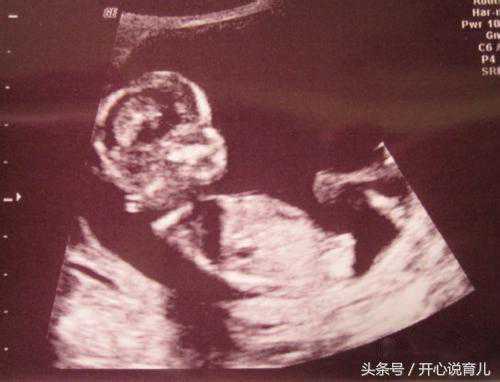

主要是检查宝宝在子宫内的发育情况是否符合孕周,胎儿是否健康,四肢、头脑、内脏发育是否畸形,以及羊水、脐带情况,在排畸B超过程中,有可能由于胎儿位置不好等情况,有些器官无法看到,这时会让孕妈下来走动,让胎儿换个位置,再重新看。(检查时间:18-24周,最好不要超过孕28周)